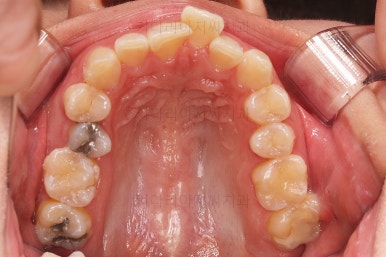

초진 시 입안의 모습입니다.

전반적으로 치열이 삐뚤고, 특정 앞니는 톡 튀어나가 미적으로 좋지 못한 상황이었습니다.

이갈이, 이악물기 습관도 있어서 앞니는 삐뚤어진 채로 치아가 많이 갈려있는 상황이었습니다.

종료 이후에는 어금니의 기존 크라운 보철이 오래되고 탈이나서 재보철을 해주었습니다.

앞니는 비뚠채로 장기간 마모가 되어온 터라 형태가 부적절하긴 한데요.

보철로 마무리하기 보다는 최대한 자연스럽게 시리지 않는 선에서 다듬어 드리고 마무리를 했습니다.